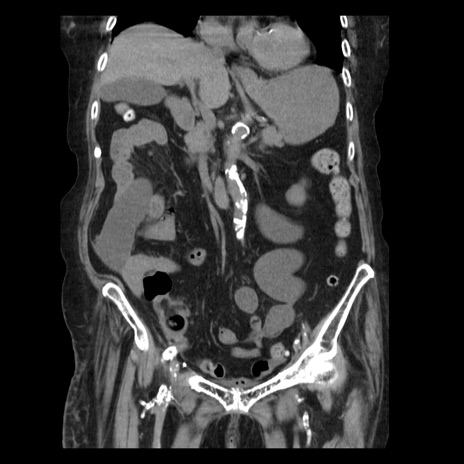

横断像